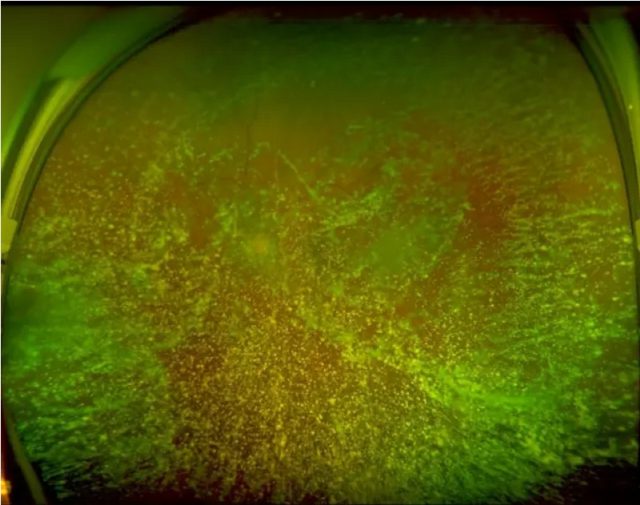

「来自星星的你」呼和浩特市朝聚眼科医院